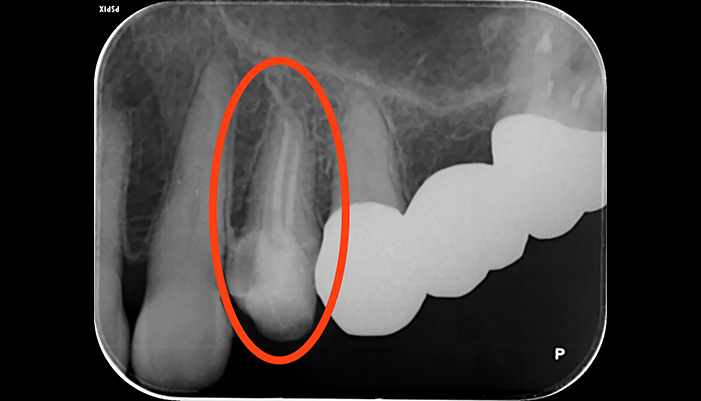

治療前

治療後

| 主訴 | 虫歯がある。根の管が細すぎて見当たらない。 |

|---|---|

| 治療期間 | 1回 |

| 費用 | 再根管治療132,000円(税込)+ ファイバーコア44,000円(税込)= 176,000円(税込) |

| 治療内容 | ラバーダムを用いて無菌的な環境下で根管治療を行いました。 マイクロスコープ下で虫歯を完全に取り切り、根の管の細さが0.06mm程度になっていたため慎重にNiTiファイルを用いて根管形成を行い、 薬液や超音波器具による洗浄、体に馴染みの良い材質による充填、被せ物を支え、再感染しないように土台を立てました。 |